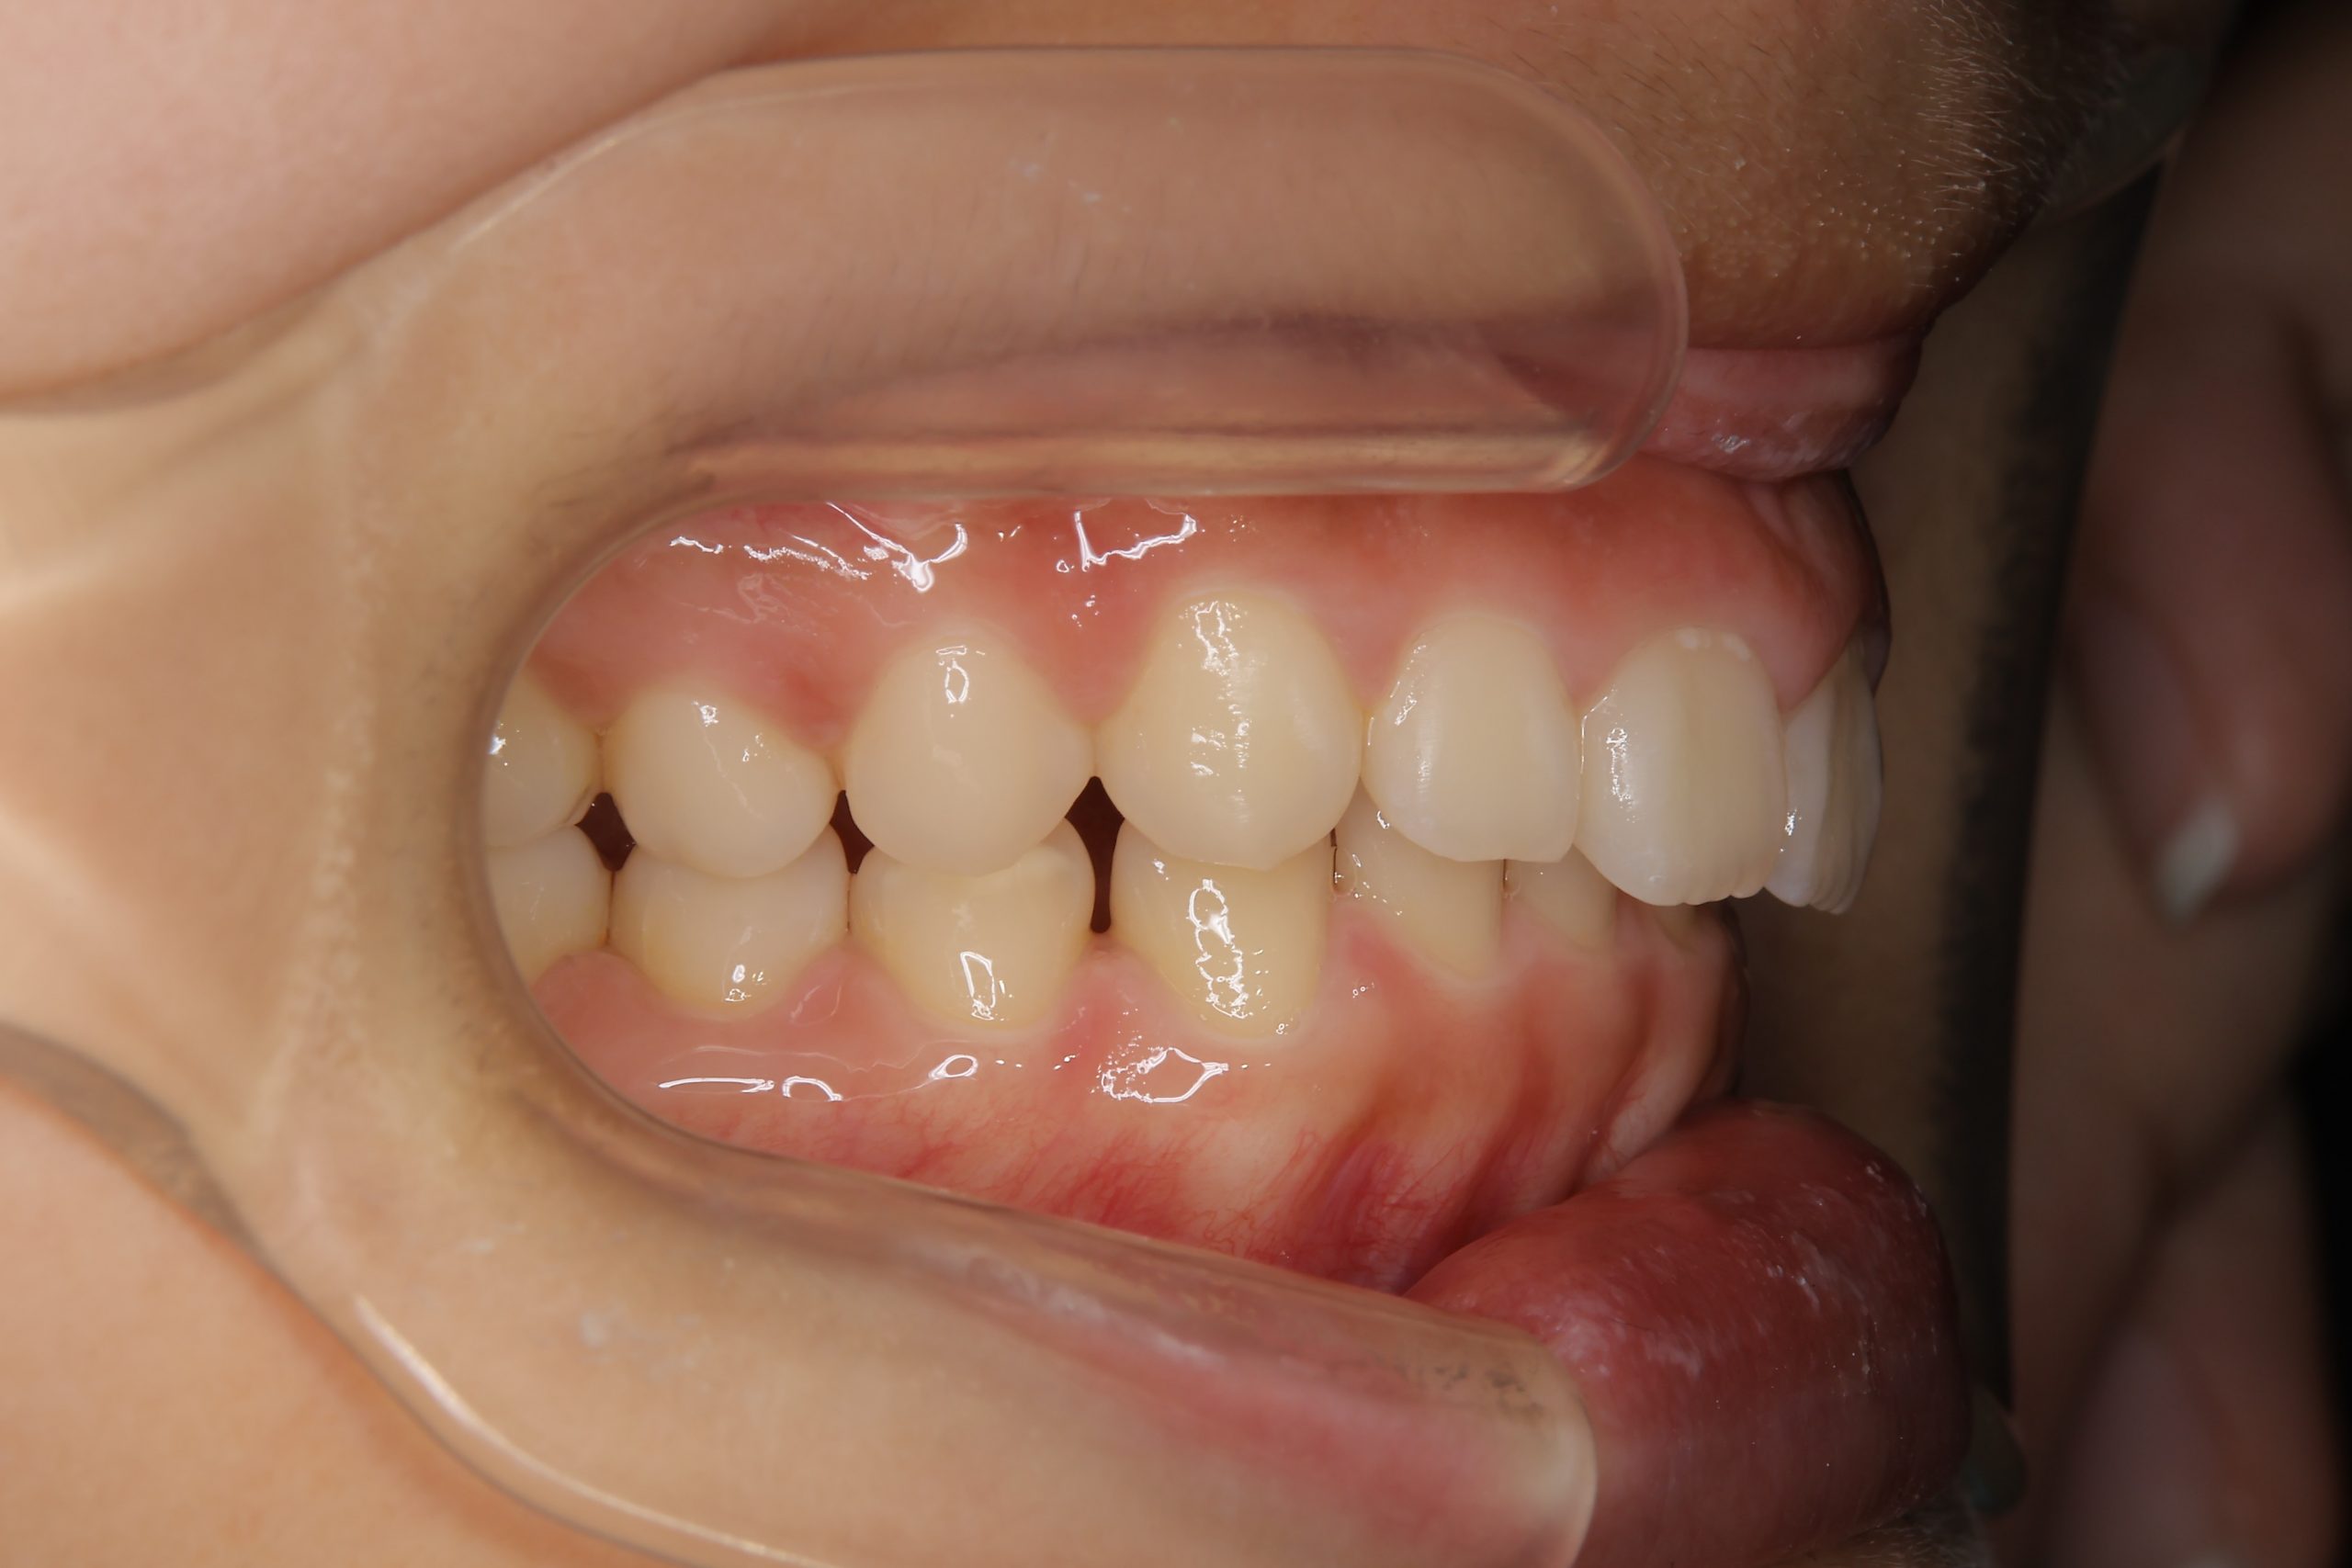

アフター

主訴 上下の歯が接触しない

施術内容 上顎急速拡大装置と下顎リンガルアーチを用いて上下顎骨を拡大した。

その後マウスピース型矯正装置で歯牙を配列し良好な咬合を獲得した。

治癒期間 2年10か月